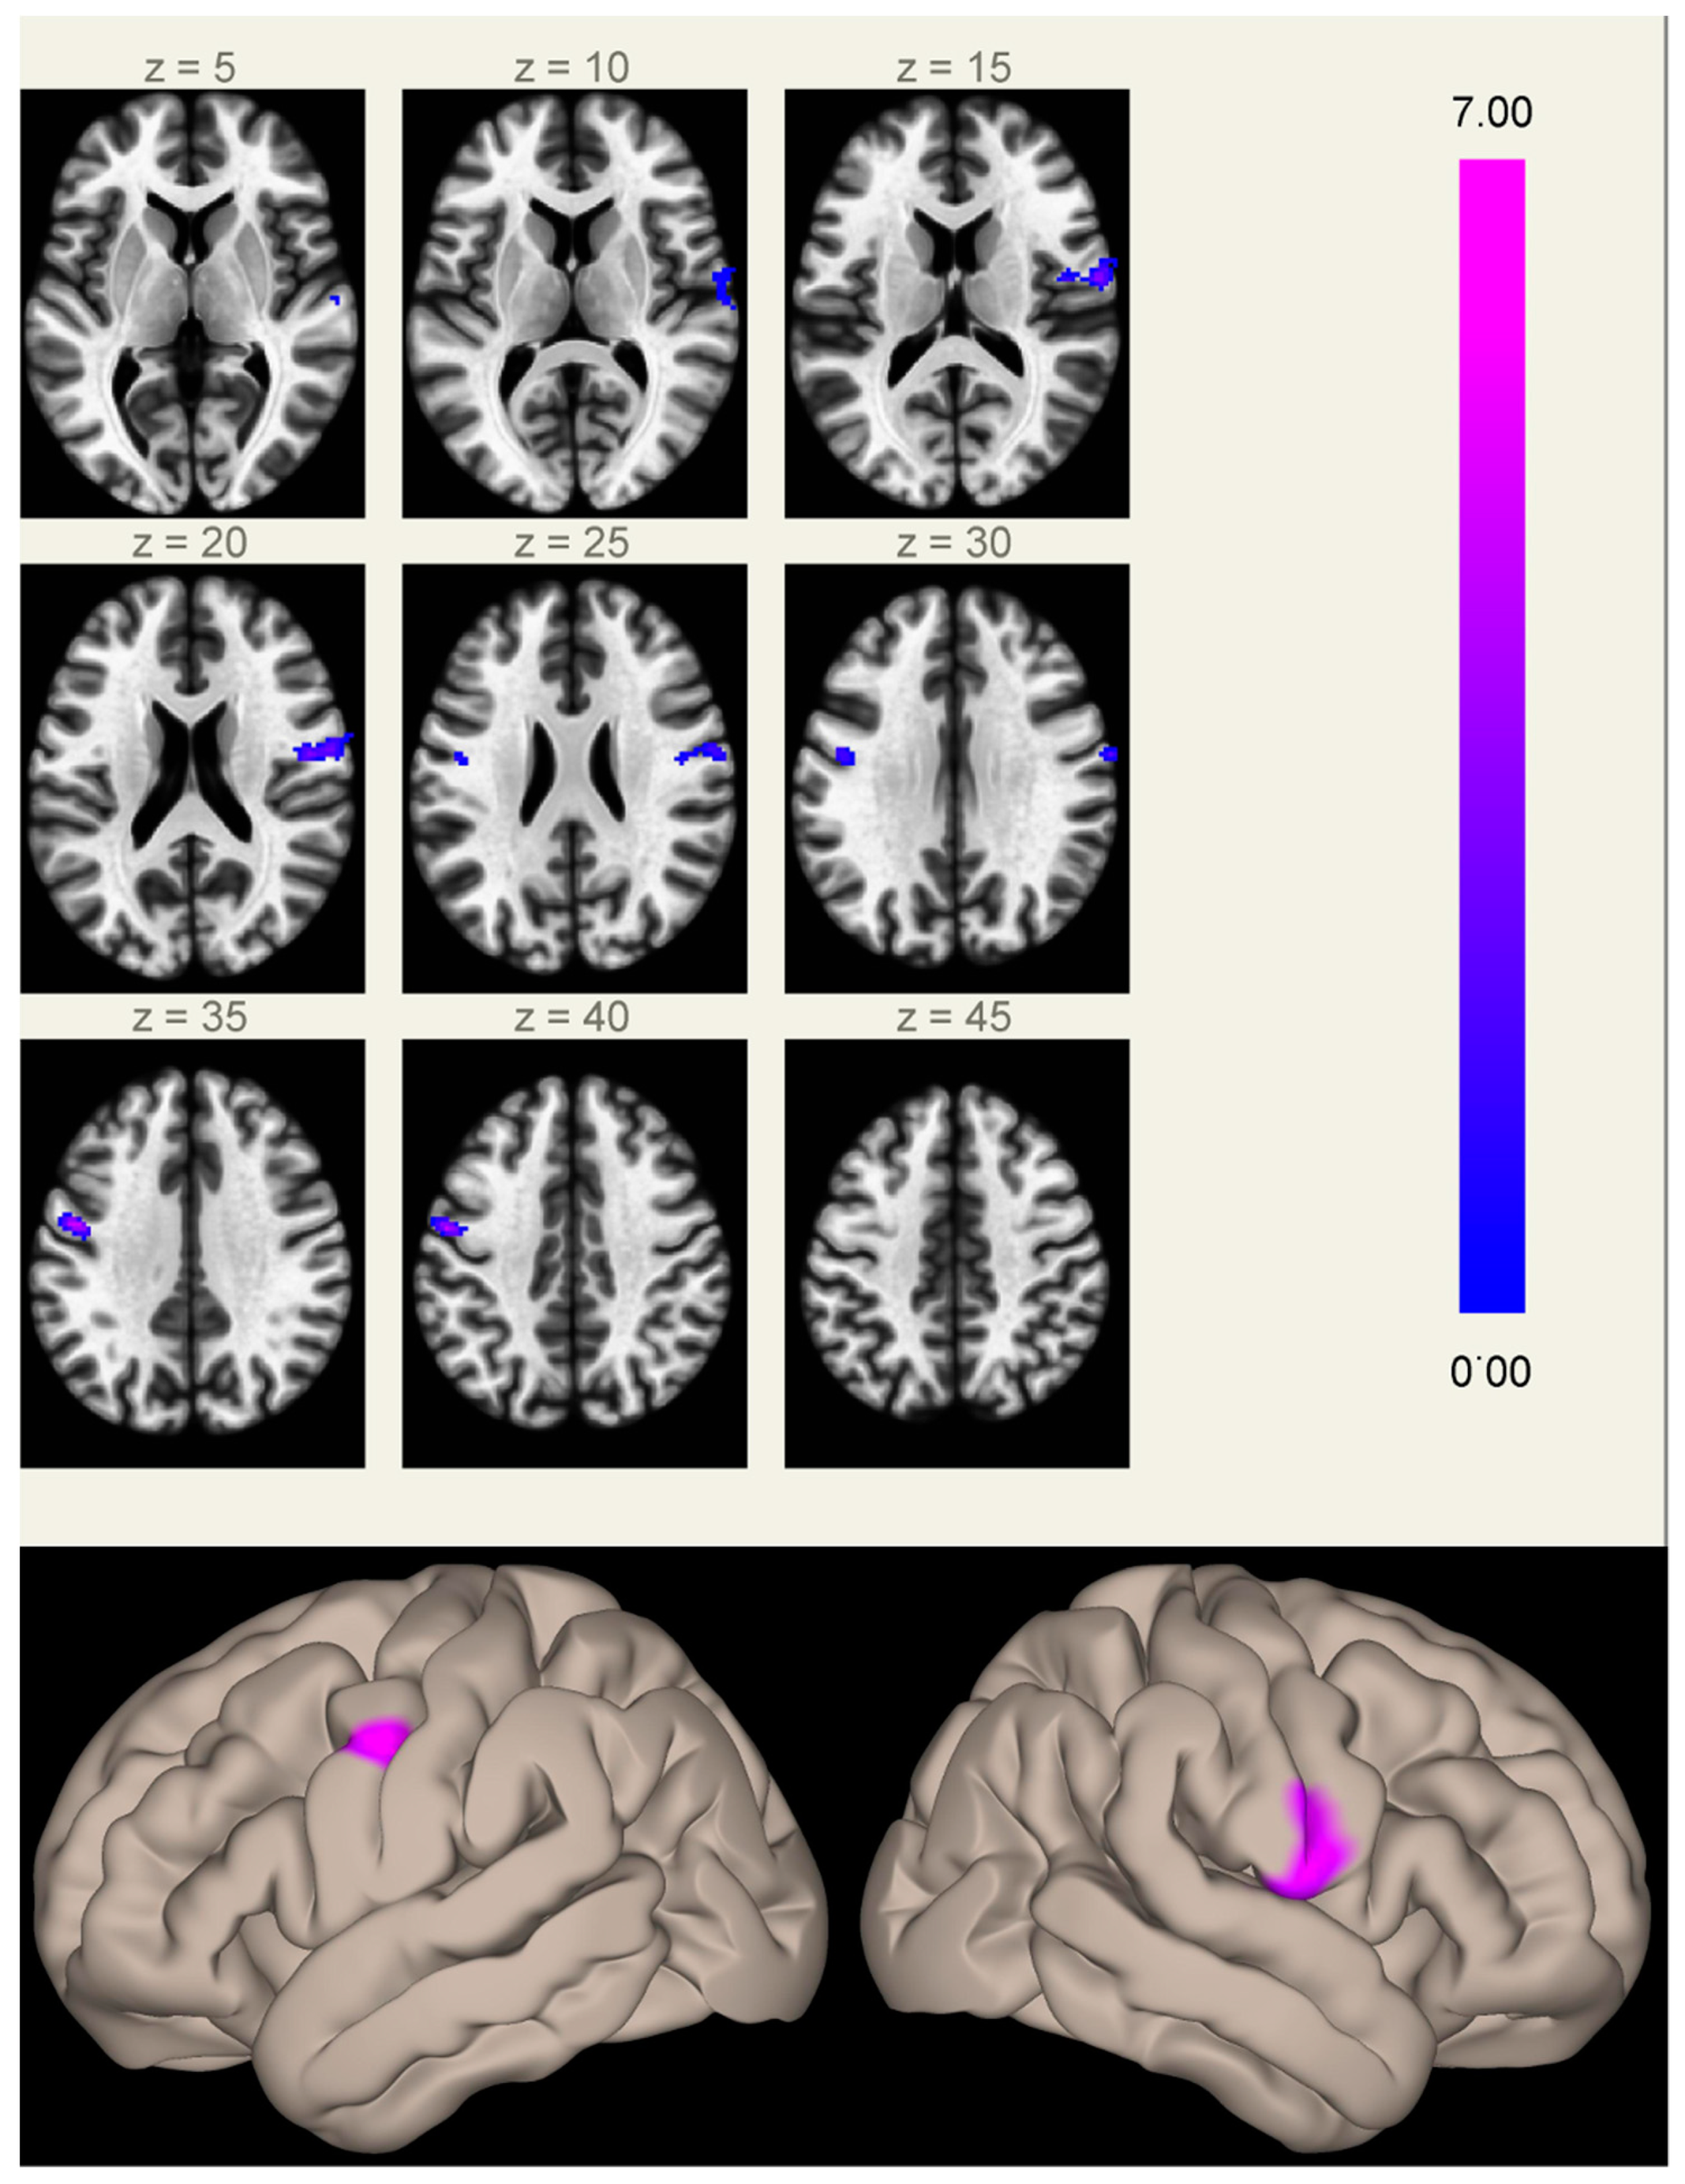

When comparing FC maps between the two groups, we found significantly increased FC between the MPFC (anterior hub of the DMN) and the inferior part of the right (2.8 cm3, p < 0.001 FWE-corrected at cluster level) and left (1.4 cm3, p < 0.05 FWE-corrected at cluster level) precentral gyri in Group A compared to Group B (Figure 1 and Figure S1). These clusters lie in regions normally devoid of significant connectivity with the DMN hubs, located between the two main regions anti-correlated to the DMN (the frontal eye field and the intraparietal sulcus), part of the task-positive network/dorsal attention network [,].

Figure 1. Clusters of increased correlation with the MPFC (anterior hub of the default mode network) in Group A compared to Group B. Significant clusters are located in the inferior part of the right (2.8 cm3, MNI coordinates of cluster maximum [+60 −06 +16]) and left (1.4 cm3, [−48 −04 +34]) precentral gyri. The color scale represents T-values from the GLM.